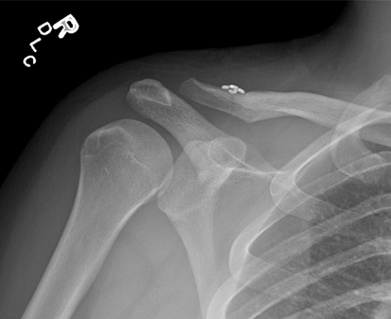

AC joint injuries are diagnosed through a combination of the history of injury, physical exam, and radiographic (x-ray) findings (Figure 2). Notice the elevated clavicle in relation to the coracoid. Symptoms consistent with those mentioned above, in combination with abnormal x-ray findings, are typically all that is required to make the diagnosis of AC joint injury.

Figure 2